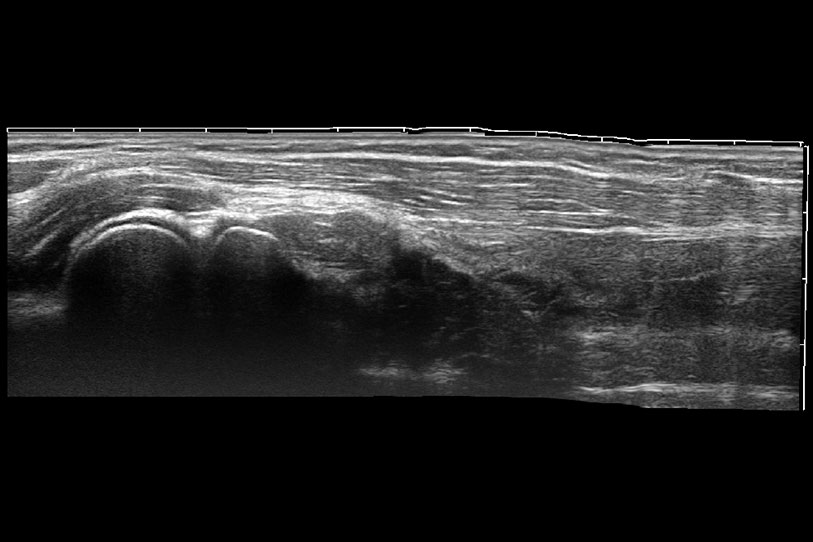

ProPet 70 进一步提升了微米成像算法,更加注重对基础原始图像的还原和保留,在有效减少斑点噪声、增强组织边界显示的同时,避免过度优化丟失真实的解剖信息。